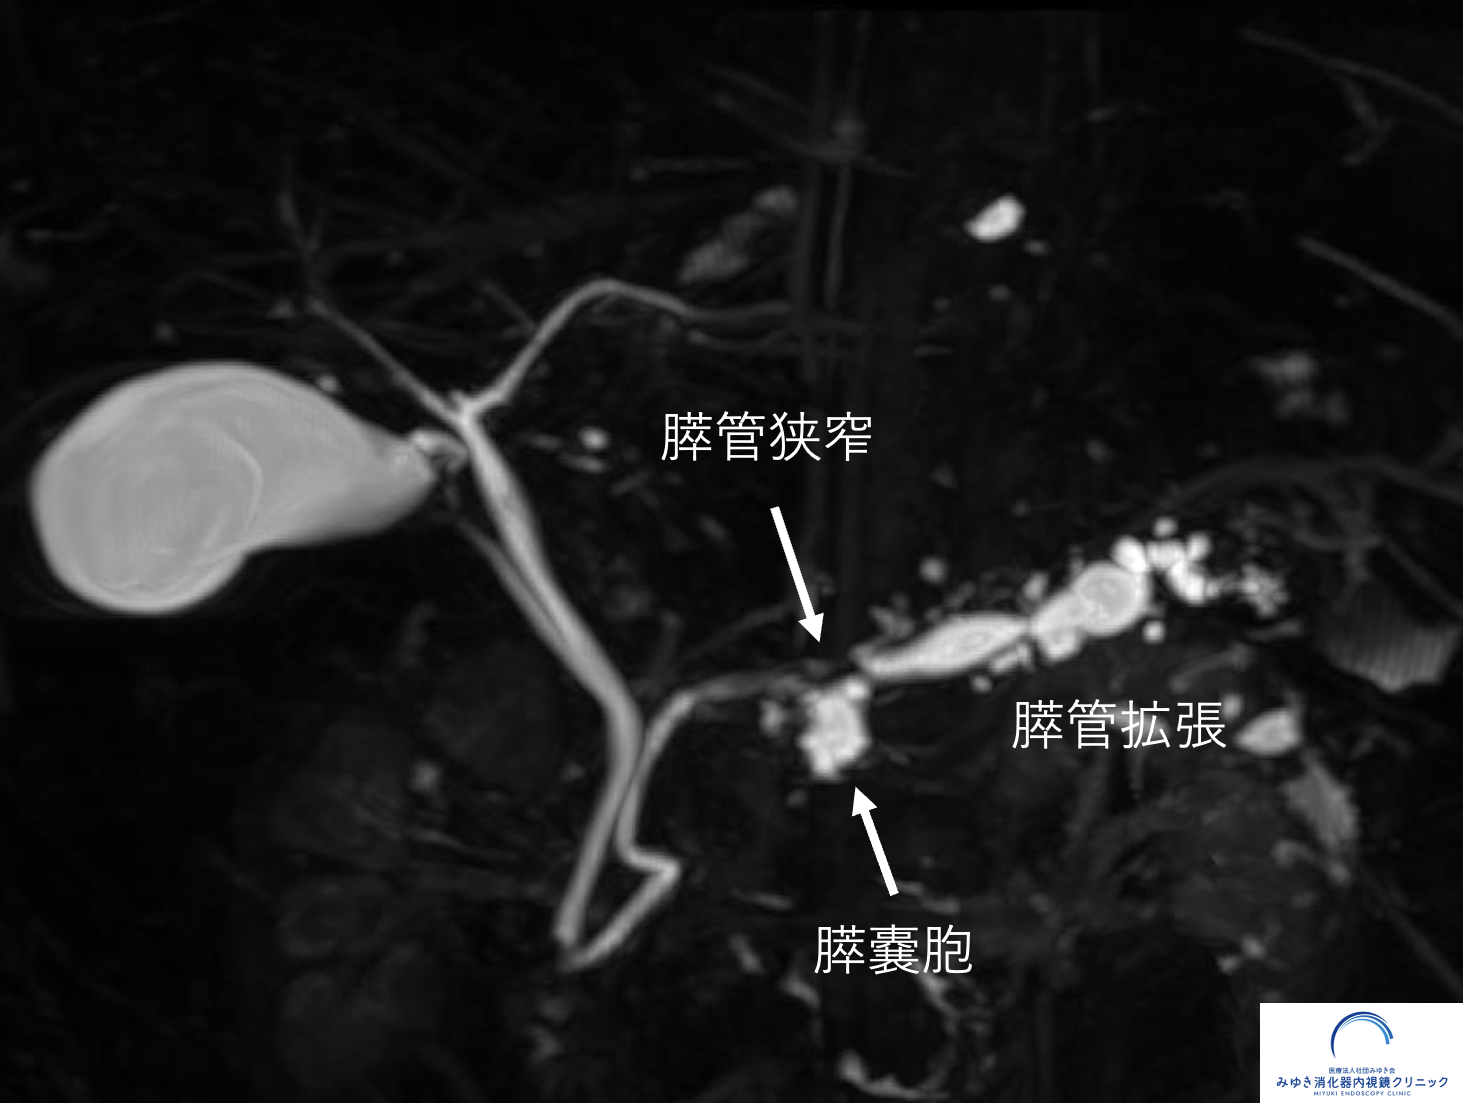

膵管拡張は、単独ではすぐに膵がんを意味するものではありません。 しかし、膵管の一部が急に細くなっていたり、上流の膵管が拡張していたりする場合には、 その背景に小さな病変が隠れていることがあります。

以下は、膵管拡張をきっかけに詳しく調べたことで、 膵上皮内がん(ステージ0膵がん)の診断につながった症例です。 MRI/MRCPで膵管の変化を確認し、さらに超音波内視鏡(EUS)で詳しく評価しています。

膵管拡張からステージ0膵がんの診断につながった症例

膵管拡張をきっかけに精密検査を行い、膵上皮内がん(ステージ0膵がん)の診断につながった症例を紹介しています。